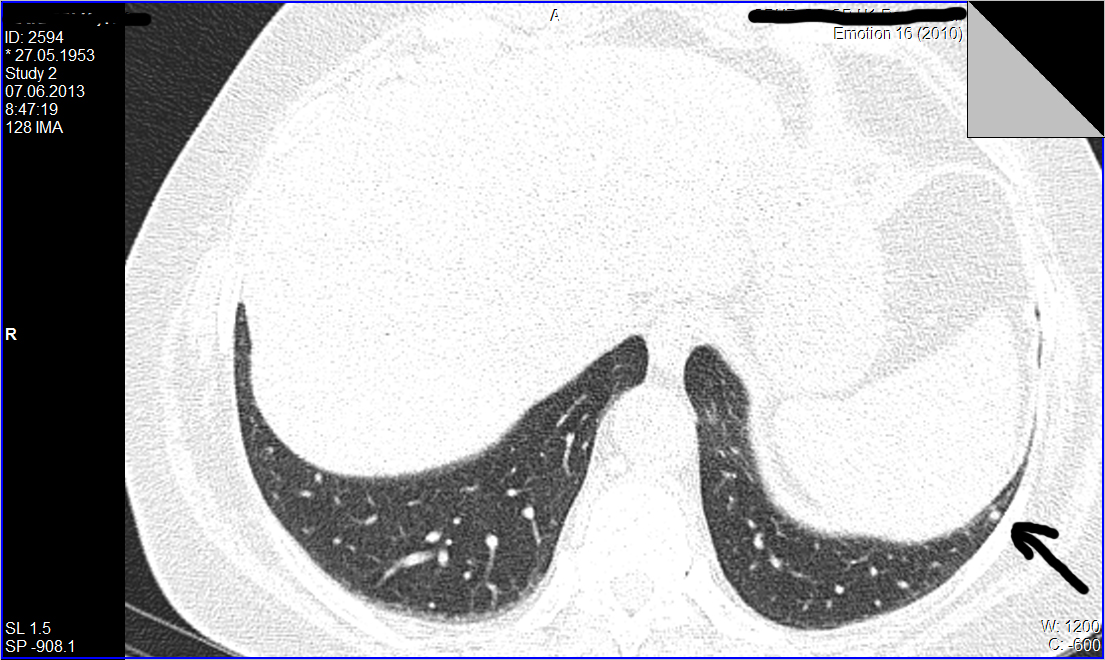

Уважаемые колеги, нужен совет более опытных чем я КТшников. А вопрос такой: как трактовать находки в виде одиночных мелких очагов в легких при относительно спокойном анамнезе.

Для примера приведу такой случай: из туб. диспансера направлена женщина после туб контакта, пожелавшая сделать кт легких. Жалоб нет, проведеные анализы без особеностей. Просмотрев томограммы я нашел только два единичных очага в базальных отделах левого легкого. Какая у вас тактика действий по поводу таких находок?